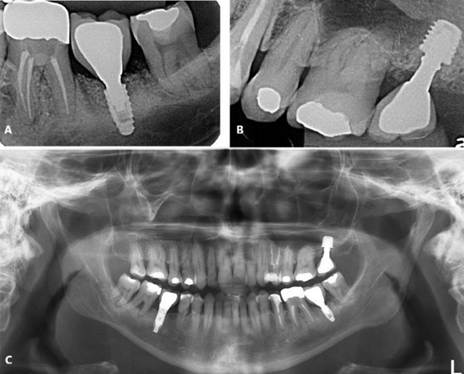

Paciente A. G. C, gênero masculino, 58 anos de idade, compareceu ao consultório particular para avaliação clínica. O paciente relatou ausência de histórico de alterações sistêmicas e de alergias. Ao exame clínico e radiográfico (Figura 10), evidenciado comprometimento dentário do 27 e do 37. O tratamento consistiu pela exodontia do 27 e 37, preservação alveolar com enxerto (Bio-Oss, Geistlinch, Wolhusen – Suíça) e membrana (Bio-Gide, Geistlinch, Wolhusen – Suíça), posterior instalação de implante extracurto ARCSYS (FGM, Joinvile – SC, Brasil) 5,0 mm x 5,0 mm na região do 27, e implantes 3,8 mm x 8,0 mmcurtos ARCSYS (FGM, Joinvile – SC, Brasil) no 37. Após 3 meses, reabilitação protética foi realizada através de próteses unitárias de cerâmica. O acompanhamento clínico e radiográfico evidencia resultado estável e satisfatório (Figura 11).

Figura 10. Radiografia panorâmica inicial.

Figura 11. A, B) Radiografia periapical final. C) Radiografia panorâmica final.